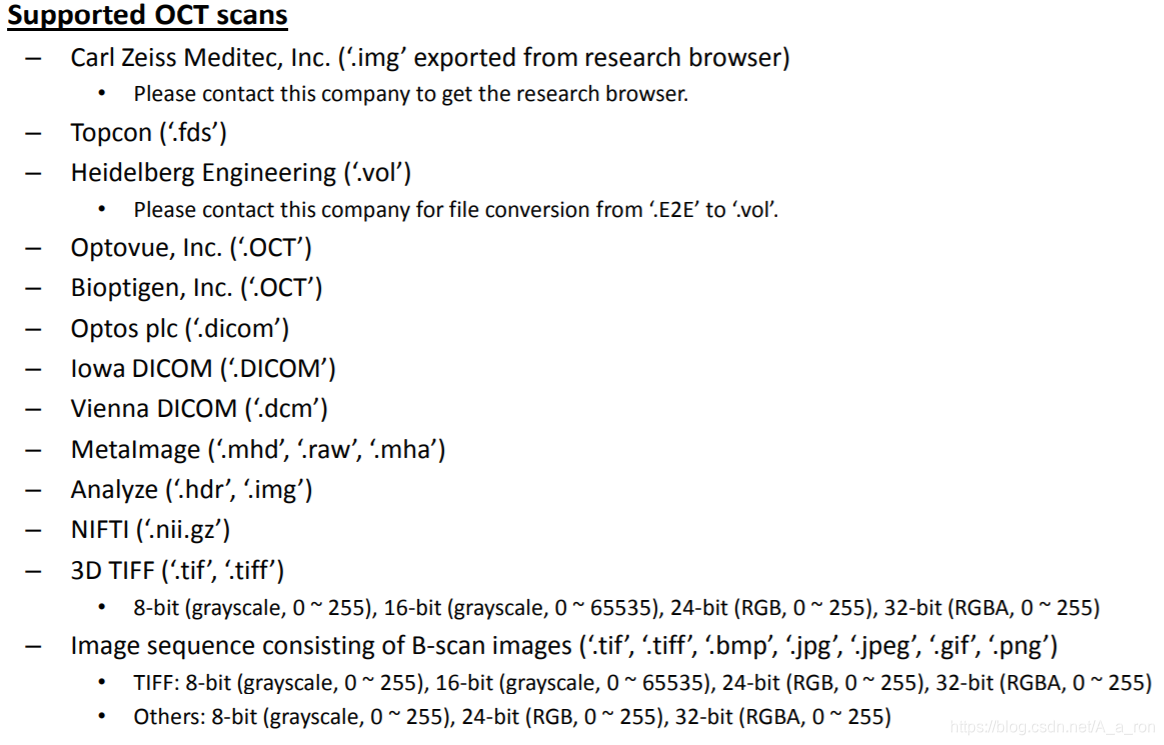

2. OCTExplorer

该软件由The Iowa Institute for Biomedical Imaging开发并维护,其包含了一系列的用于OCT影像处理的算法(目前仅支持windows平台)。软件持续得到更新,目前已经到了5.0.0版本。想要下载的话,只要同意相关的协议条款即可。同时,该软件也配置了较为详细的用户说明手册,对用户还是挺友好的。

而且该软件支持的格式非常全面,几乎适用大多数场景。

2.1 软件界面示例